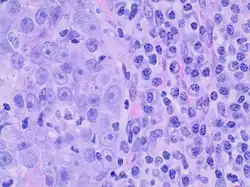

Medullary breast carcinoma is a rare type of breast cancer[1] that is characterized as a relatively circumscribed tumor [2] with pushing, rather than infiltrating, margins. It is histologically characterized as poorly differentiated cells with abundant cytoplasm and pleomorphic high grade vesicular nuclei.[3] It involves lymphocytic (a type of white blood cell) infiltration[4] in and around the tumor and can appear to be brown in appearance with necrosis and hemorrhage.[5] Prognosis is measured through staging but can often be treated successfully and has a better prognosis than other infiltrating breast carcinomas.

Criteria must be met through the Ridolfi criteria. Although there are other classifications for diagnosis, the Ridolfi criteria are the most commonly used. There must be histologic evidence of lymphoplasmacytic infiltration, noninvasive microscopic circumscription, greater than 75% syncytial growth pattern, and high-grade nuclei.[5] It is immunologically typically triple-negative, with negative estrogen receptors (ER), negative progesterone receptors (PR), and negative HER2/neu receptors.[3] There are also medullary breast carcinomas that are found to be estrogen receptors (ER) and/or progesterone receptor (PR) positive, making diagnosis less straightforward.